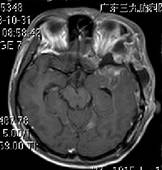

给予依达拉奉抗血管源性水肿,厄贝沙坦、倍它乐克降压及加强对症支持治疗1周。复查头颅MRI(见图三)病灶明显好转。

■ 术后MR